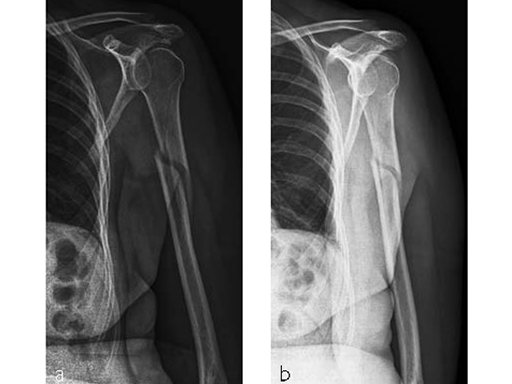

Case 2: Three-part valgus displaced fracture of the proximal humerus in a 63-year-old man.

The tuberosities have been reduced and fixed using intertubercular sutures (Fig 4). To reconstruct the medial support a calcar screw has been used. This determines the height of the nail. Therefore a 1 cm end cap has been used to get support for the proximal end of the nail in the part of the bone with the best bone quality.

Case provided by Stefaan Nijs, Leuven, Belgium